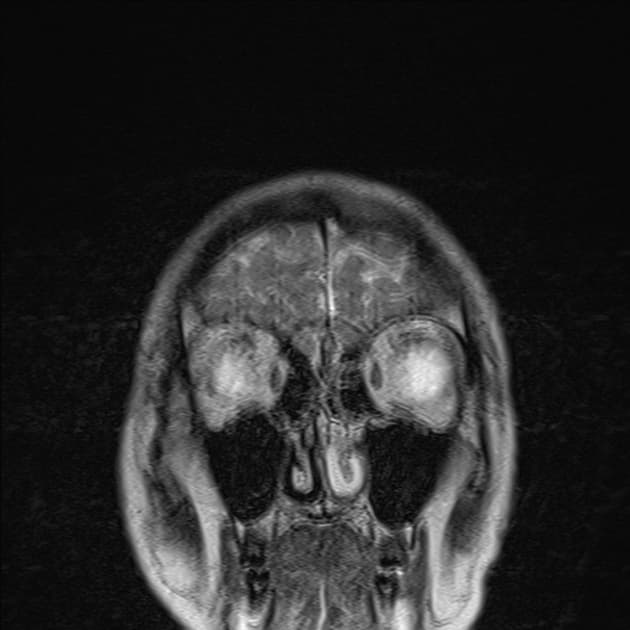

- Khối liên tục với cuống yên, làm giãn cuống này cả phía trên và phía dưới.

- Phù hợp với kiểu tăng quang đặc trưng và nằm trong cuống yên (infundibulum).

- Khối phù hợp với kiểu tăng quang đặc trưng và nằm trong cuống yên (infundibulum).

- Khối liên tục với cuống yên, làm giãn cuống cả phía trên và phía dưới.

- "Đặc điểm hình ảnh gồm khối u ranh giới rõ, tăng quang mạnh, liên tục với và làm giãn cuống yên."

U Pituicytoma là một loại khối u thần kinh đệm lành tính, phát triển chậm và hiếm gặp, xuất phát từ các tế bào pituicyte ở thùy sau tuyến yên hoặc cuống yên. Khối u thường biểu hiện như một tổn thương ranh giới rõ, tăng quang mạnh và liên tục với, đồng thời làm giãn cuống yên. Trên cộng hưởng từ (MRI), khối u thường có tín hiệu đẳng trên hình ảnh T1 và tăng quang đồng nhất sau khi tiêm thuốc cản quang. Việc không có dấu hiệu ác tính, không bệnh toàn thân và tổn thương ổn định dài hạn trên hình ảnh học làm tăng khả năng chẩn đoán u Pituicytoma, ngay cả khi chưa xác định bằng mô bệnh học. Các chẩn đoán phân biệt bao gồm u tuyến yên có liên quan đến cuống yên, u màng não và bệnh tổ chức bào Langerhans, những bệnh này có thể có hình ảnh tương tự. Tuy nhiên, vị trí đặc hiệu trong cuống yên và sự liên tục với cuống làm nghiêng về chẩn đoán u Pituicytoma. Điều trị thường mang tính theo dõi bảo tồn, đặc biệt ở bệnh nhân không có triệu chứng.